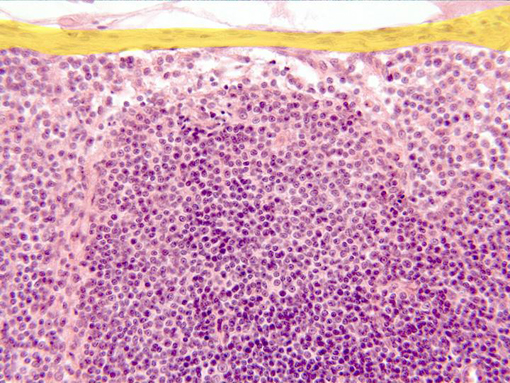

Aspect of the zone next to the ganglionary

capsule (yellow)

observed with the objective of 40x. Under the capsule appear

the

subcapsular sine,

a looser arranged zone, and immediately underneath is

situated part of a

lymphatic follicle,

containing numerous lymphocytes showing blue-stained nuclei